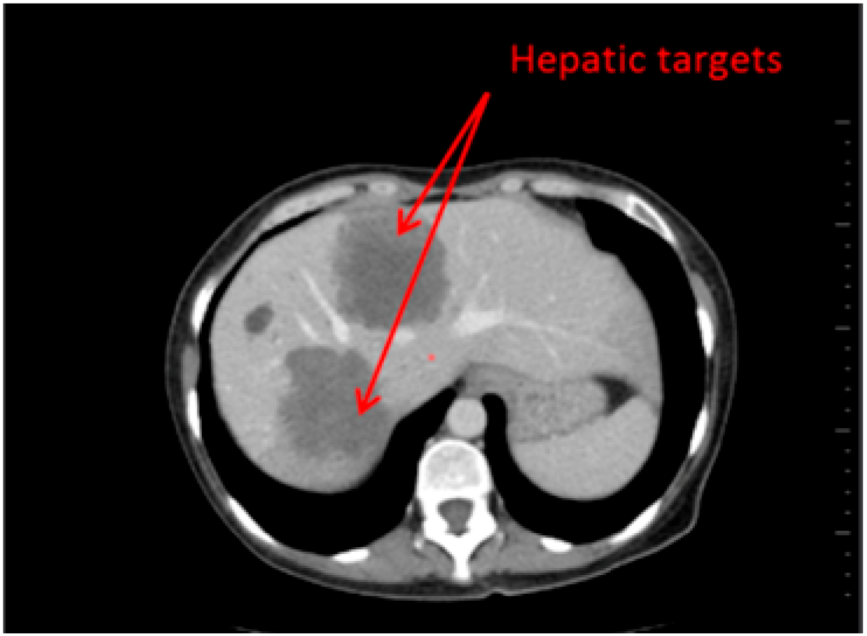

- 3D target matching technology to facilitate lesion localisation in the follow up study.

| Step 3 | Target localisation on baseline study | Manual | Automated |

| Step 4 | Target localisation on follow up study | Manual | Automated |